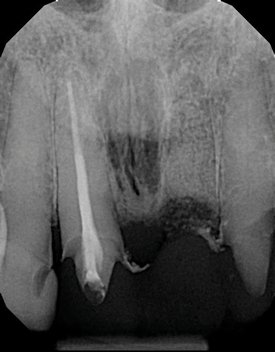

The idea that a dentist may be incorrect in his or her diagnosis is distasteful, but a reality that this profession wrestles with on a daily basis. An image comparison can help to clarify this thought. The first image is a 2D radiograph of tooth No. 19 that includes the buccal cortical plate the lingual cortical plate and approximately 10 mm of trabecular bone compressed into a single image (Figure 1). Because the full width and volume of the tooth is included in the image, any existing pathoses could be masked or hidden in a fog of digital information. A CBCT scan of the same tooth provides more detail because it can present a slice (0.1 mm) of information from the center of the area in question (Figure 2). All of the extraneous information is eliminated, and the clinician and the patient have a more precise picture to evaluate. Furthermore, a periapical radiograph can be distorted by the angle of the cone to the sensor, whereas a CBCT scan has no distortion and is accurate in all views. With a CBCT scan, the clinician is able to state with certainty that a condition exists, and the patient is able to more clearly understand what his or her condition is when considering the available choices for treatment.

(1. ) Two-dimensional periapical radiograph of tooth No. 19 compared with a CBCT scan slice (0.1 mm) of the same tooth, which reveals a well-defined lesion that a patient can more easily understand.

Figure 1

(2.) Two-dimensional periapical radiograph of tooth No. 19 compared with a CBCT scan slice (0.1 mm) of the same tooth, which reveals a well-defined lesion that a patient can more easily understand.

Figure 2